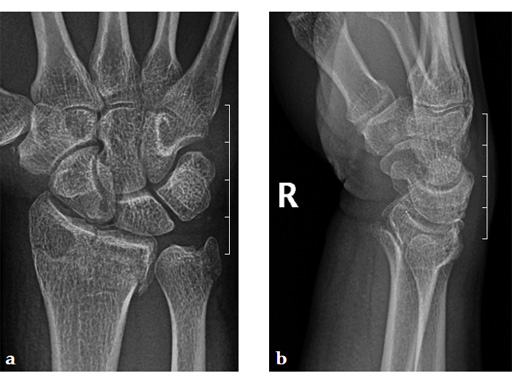

Case 2: A 44-year-old man sustained polytrauma following a car accident. Among his injuries was a distal radial fracture, Mller AO Classification 23-C1.

Case provided by Vitezslav Ruber, Brno, Czech Republic